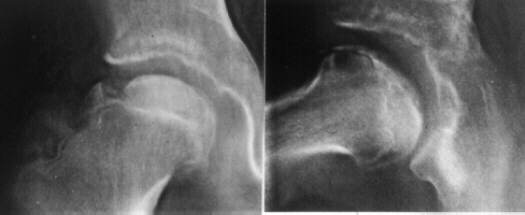

- Sugioka classifed the preoperative hips into four grades:

grade 1, necrosis just visible, the femoral head is still round;

grade 2, the head is flattened; grade 3, the head is markedly

collapsed without narrowing of the joint space; and grade 4, the

head shows advanced changes with narrowing of the joint space.

- The success rate in the 23 hips of grade1 was 91%, in the

16 hips of grade 2 was 88%, in the 64 hips of grade3 was 73%,

and in the 25 hips of grade 4 was 68%.